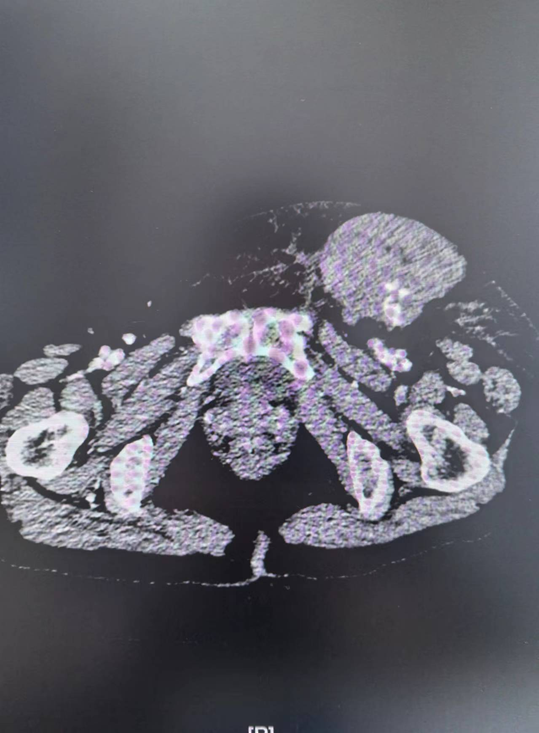

患者周xx,女性,50岁。心内科行冠脉造影术后,出现左腹股沟肿块,考虑左侧股浅动脉假性动脉瘤,遂转入我院就诊。